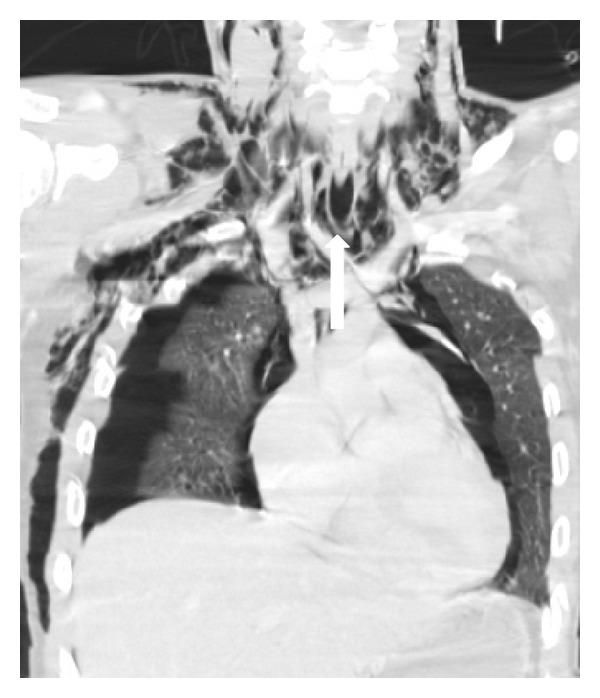

Imaging plays an essential part of chest trauma care. By definition, the employed imaging technique in the emergency setting should reach the correct diagnosis as fast as possible. In severe chest blunt trauma, multidetector computer tomography (MDCT) has become part of the initial workup, mainly due to its high sensitivity and diagnostic accuracy of the technique for the detection and characterization of thoracic injuries and also due to its wide availability in tertiary care centers. The aim of this paper is to review and illustrate a spectrum of characteristic MDCT findings of blunt traumatic injuries of the chest including the lungs, mediastinum, pleural space, and chest wall.

影像学在胸部创伤治疗中起着至关重要的作用。根据定义,在急诊环境中所采用的影像学技术应尽快得出正确诊断。在严重胸部钝性创伤中,多排螺旋计算机断层扫描(MDCT)已成为初始检查的一部分,这主要归因于该技术在检测和鉴别胸部损伤方面具有高敏感性和诊断准确性,还归因于其在三级医疗中心广泛可用。本文旨在回顾并阐述胸部钝性创伤包括肺、纵隔、胸膜腔和胸壁的一系列MDCT特征性表现。